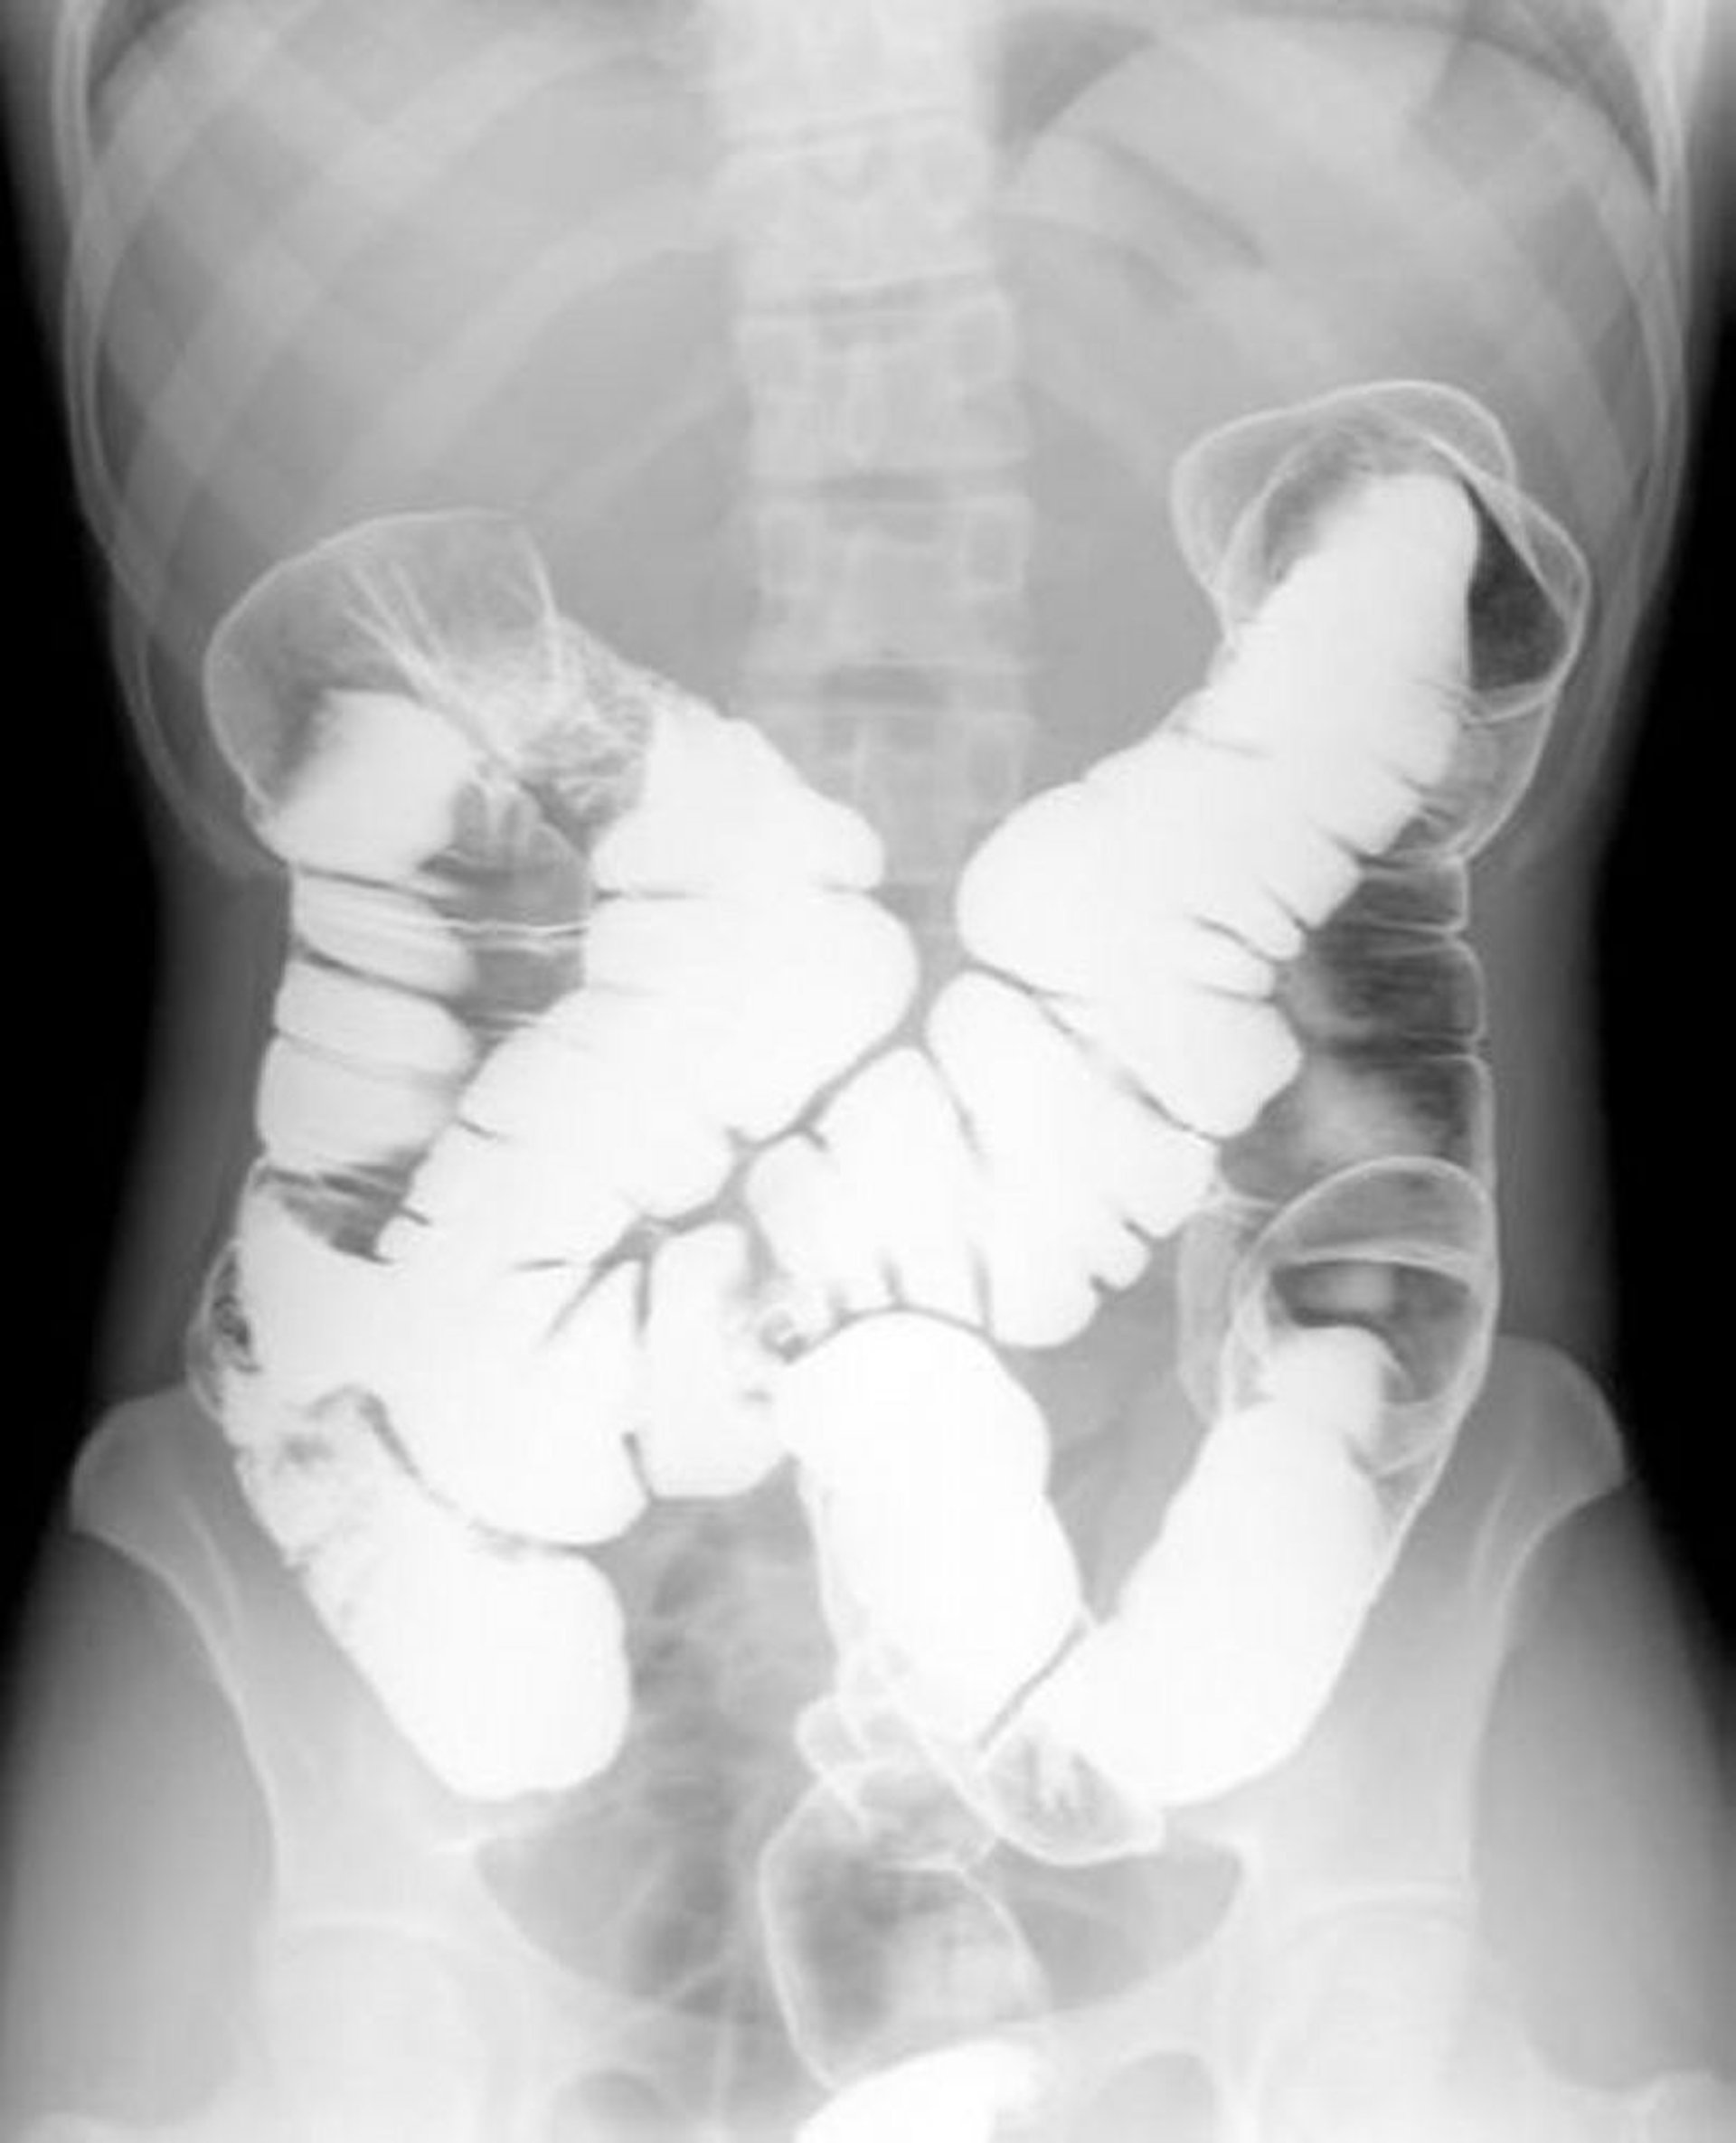

Thuốc xổ bari thuốc cản quang kép cho thấy giải phẫu bình thường

Hình ảnh này cho thấy mô hình của không khí và bari trong một đại tràng bình thường.